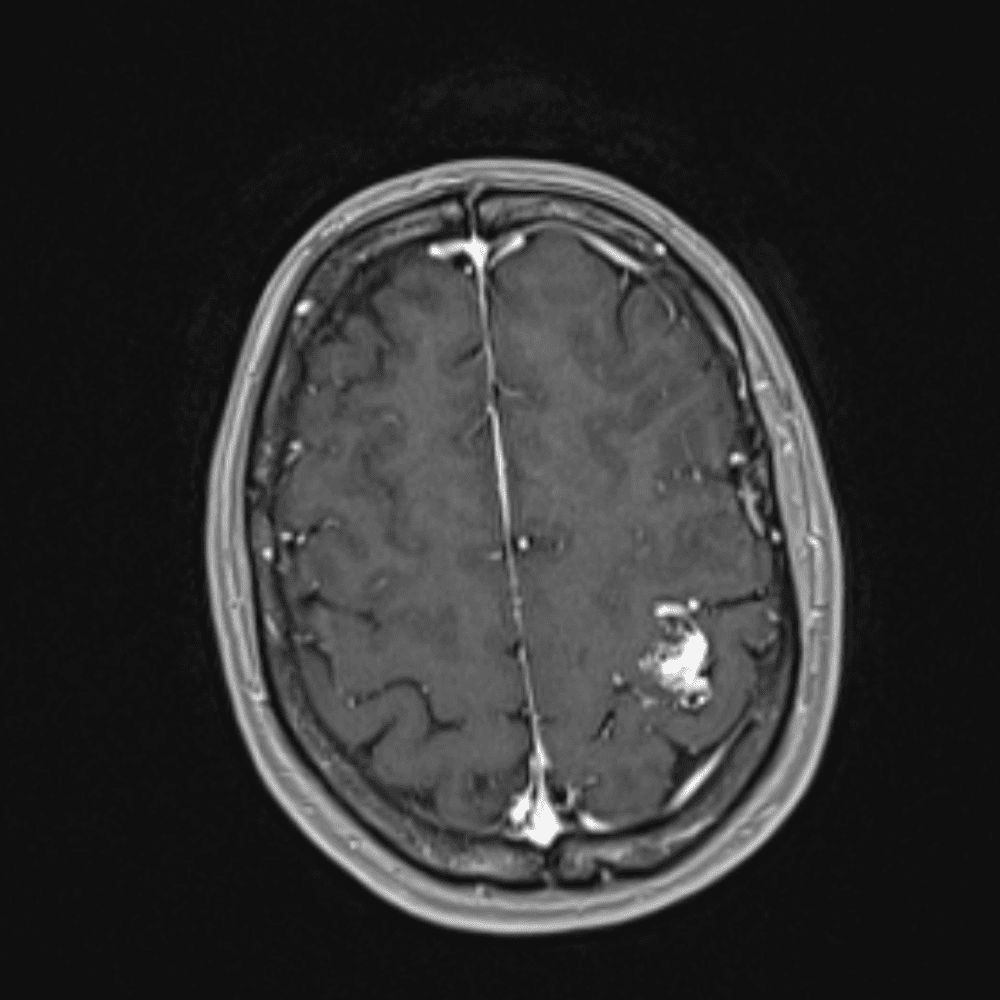

๋‹น์ง ์‹œ ํ”ํžˆ ๋ณผ ์ˆ˜ ์žˆ๋Š” ์‚ฌ๋ก€์˜ ์ „ํ˜•์ ์ธ ์˜ˆ๋ฅผ ํฌํ•จํ•ฉ๋‹ˆ๋‹ค.

39 ์‚ฌ๋ก€

์—ฐ์Šต

๋ฏธ๋ฌ˜ํ•˜๊ฑฐ๋‚˜ ์–ด๋ ค์šด ์‚ฌ๋ก€์™€ ์ผ๋ถ€ ์ •์ƒ ์‚ฌ๋ก€๋ฅผ ํฌํ•จํ•˜์—ฌ ๋‹น์ง์„ ์‹œ๋ฎฌ๋ ˆ์ด์…˜ํ•ฉ๋‹ˆ๋‹ค.

50 ์‚ฌ๋ก€